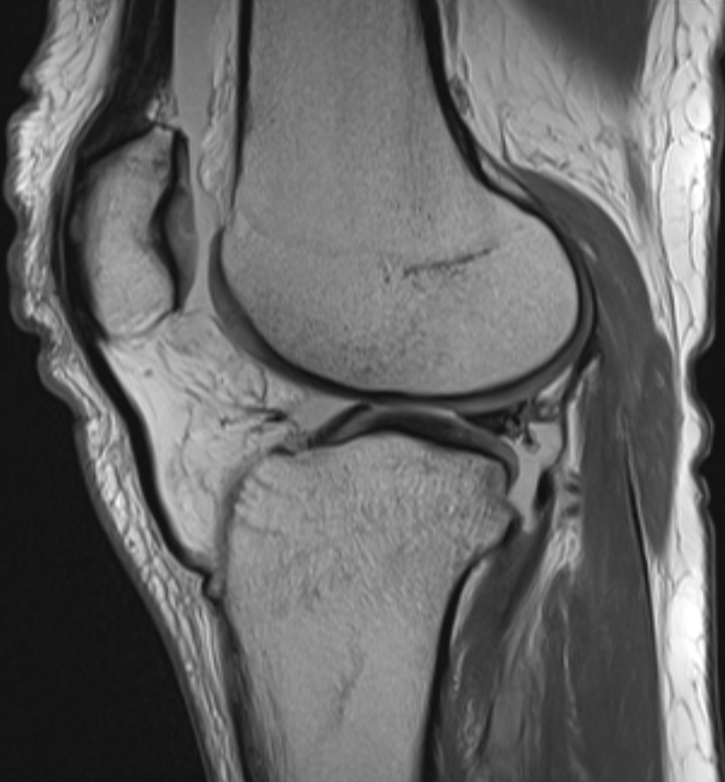

3. Posterior meniscocapsular ligament injury